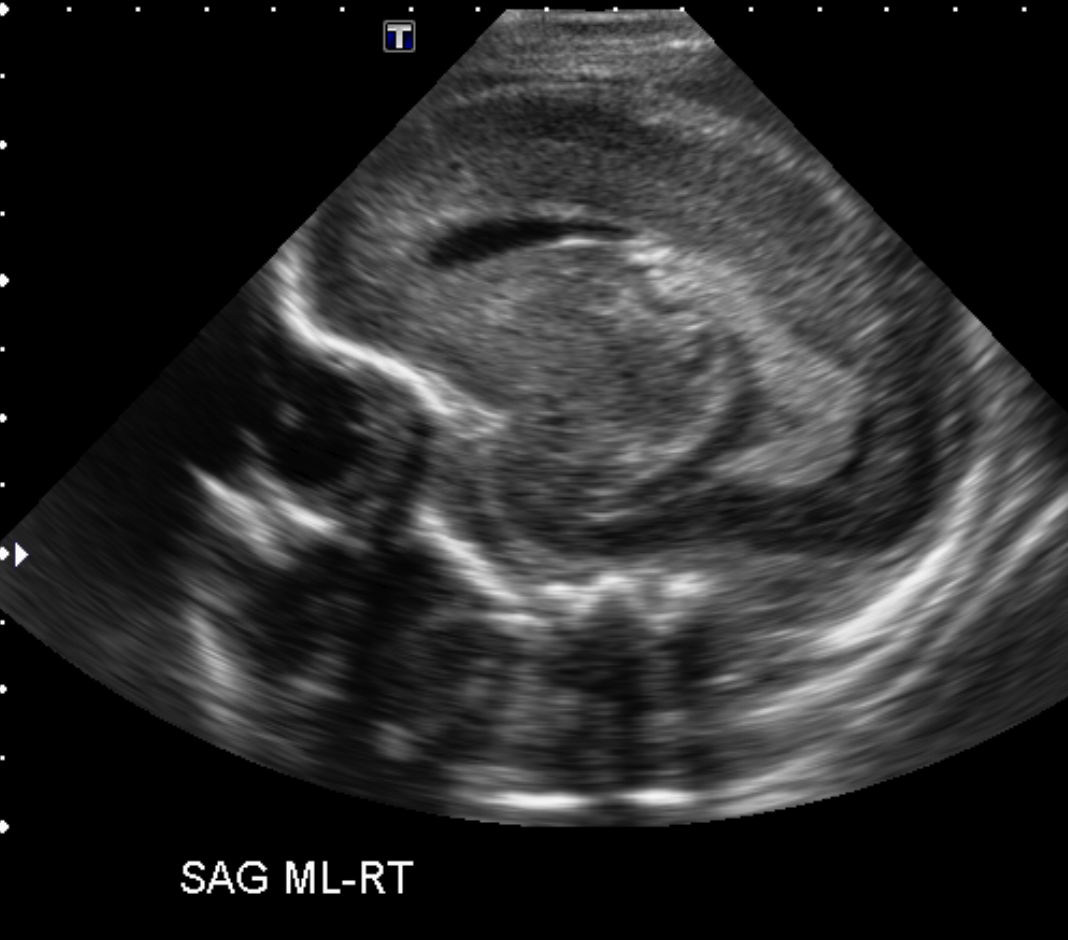

CSF spaces/ventricular system

There is prominence of the ventricular system. [Yes/No]

There is an asymmetry of the ventricular system. [Yes/No]

The lateral ventricle/s are dilated. [Yes/No]

The third ventricle is dilated. [Yes/No]

The 4th ventricle is dilated. [Yes/No]

The choroid plexus is bulky/lobulated. [Yes/No]

There is a choroid plexus cyst measuring… [Yes/No]

There are debris/clots in the occipital horn. [Yes/No]

There is a posterior fossa cyst measuring… [Yes/No]

The tentorium is elevated/depressed. [Yes/No]